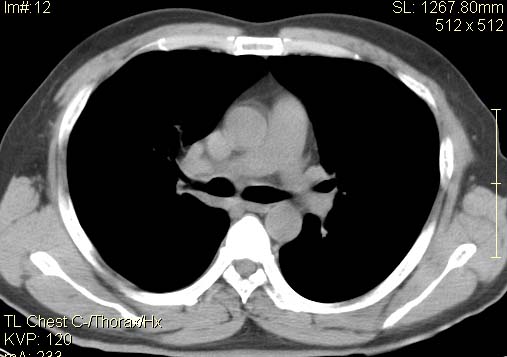

以下是引用qc80012345在2007-4-17 12:33:00的发言:[br]右肺下叶周围型肺癌伴肺门及纵隔内淋巴结转移;比较清楚。

以下是引用qingyuan在2007-4-17 14:19:00的发言:[br]右肺下叶外侧后段胸膜下区节结样病变、分叶、内可见空洞,壁厚薄不均,胸膜凹陷、肺门周围区纹理增粗、僵硬、并近似小结节样改变,肺门区软组织节结、纵膈淋巴结肿大,患者病史长、抗炎治疗无好转炎性改变基本排除,考虑:右肺下叶周围型肺癌伴纵膈及右肺门区淋巴结转移、肺内淋巴管受侵。